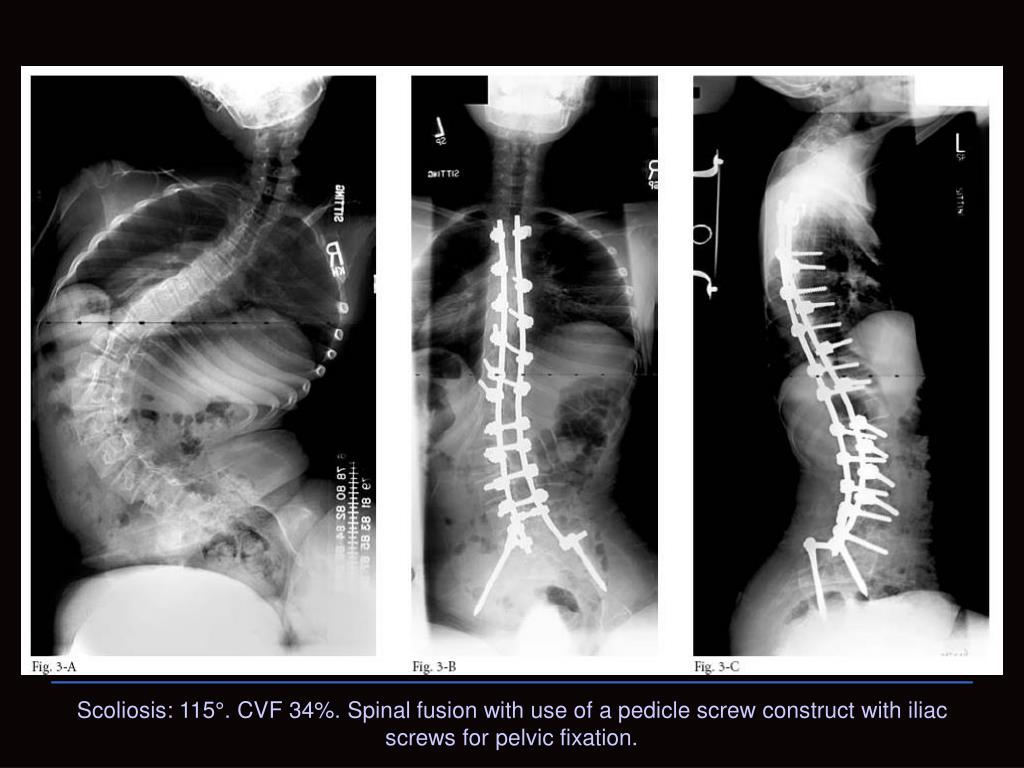

22. Scoliosis: 115°. CVF 34%. Spinal fusion with use of a pedicle screw construct with iliac screws for pelvic fixation.

23. Manejo de la escoliosis • Miller et al. encontró complicaciones pulmonares en 20 de 68 pacientes. La CVF <35% de lo normal fue el mayor indicador de riesgo para complicaciones. • Se requiere una nueva evaluación postoperatoria por terapia ocupacional para evitar la malnutrición. • El desarrollo de insuficiencia cardiaca es fatal, se ha descrito varios casos de muerte súbita post-Qx. Miller 1993, Marsh 2003, Iannaccone 2003, Granata 1996